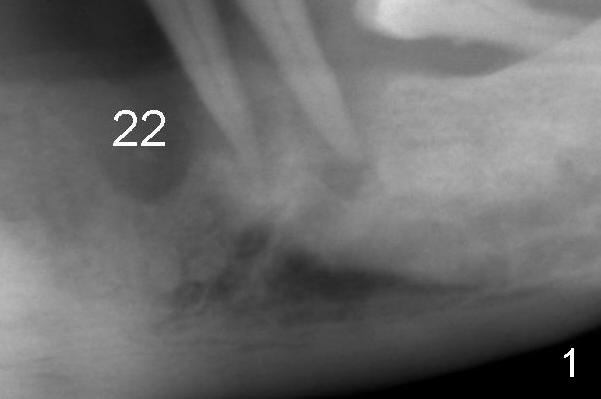

Fig.1: There appears to be triple mental nerve loops below the lower left canine and premolars. Return to